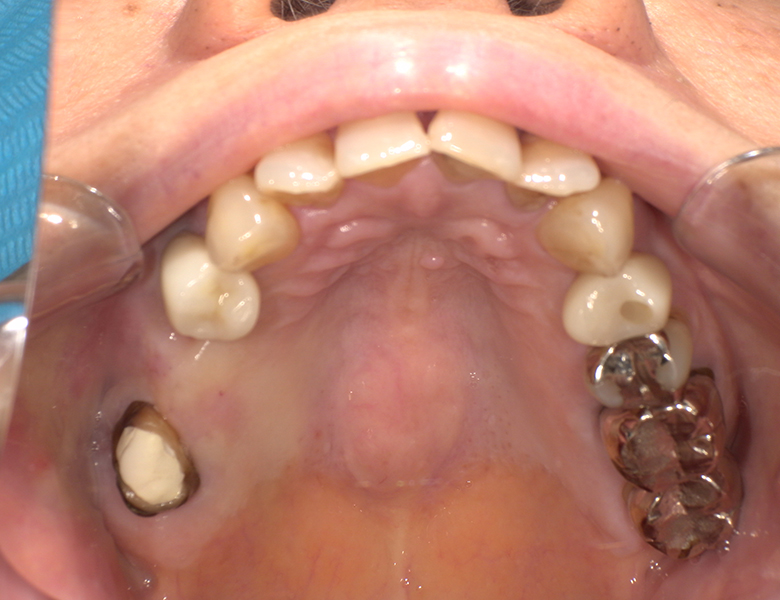

治療前 ![]() |

上顎奥歯で噛みにくさがあり、食事のしづらさを感じて来院されました。あわせて、欠損部をしっかり噛める状態に回復したいというご希望がありました。 |

上顎右側の奥歯(14・16部位)が欠損しており、咀嚼機能の低下が認められました。部分入れ歯という選択肢も考えられましたが、装着感や安定性、残存歯への負担を考慮すると、固定式の治療が望ましい状態でした。 |